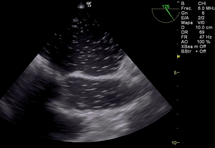

Reconocer un ritmo de fibrilación ventricular y actuar desfibrilando de inmediato es el principal objetivo (Figura b), pero a continuación analizar la causa de la fibrilación, por ejemplo el ingreso de aire en la arteria coronaria derecha cuyo tratamiento es aumentar la presión de perfusión coronaria, reingresar a CEC y/o agregar s inotrópicos para aumentar la contractilidad; o una isquemia aguda de dicha arteria que lleva a la necesidad de realizar un puente venoso, tal es el caso de reconocer con ETE el signo de McConnel o signos de aumento de presión de cavidades derechas17. El aire puede ingresar también hacia la arteria pulmonar y observar esta situación a través de ETE nos obliga a informar al cirujano para lograr la completa desairación 18. (Figura cyFigura d)

Figura d: imagen medioesofágica 0 grado de arteria pulmonar aire en su tronco principal y ramas derecha e izquierda.